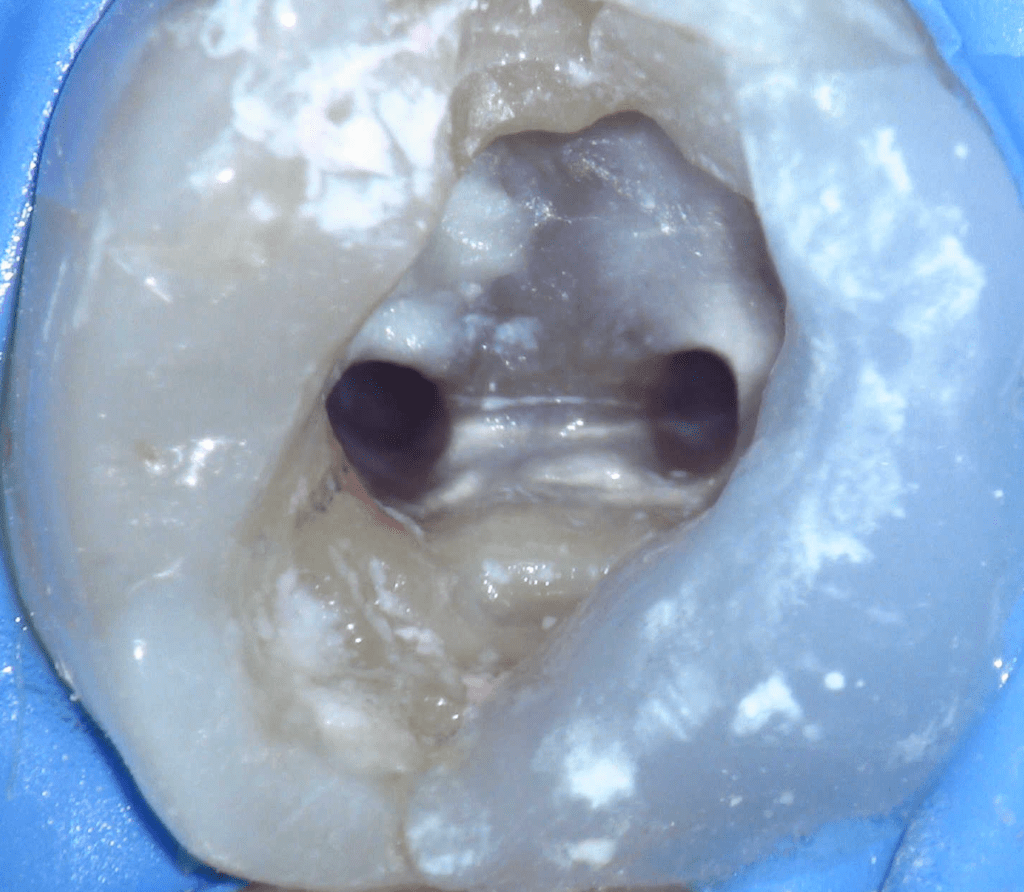

Reco pre-endo, molar inferior